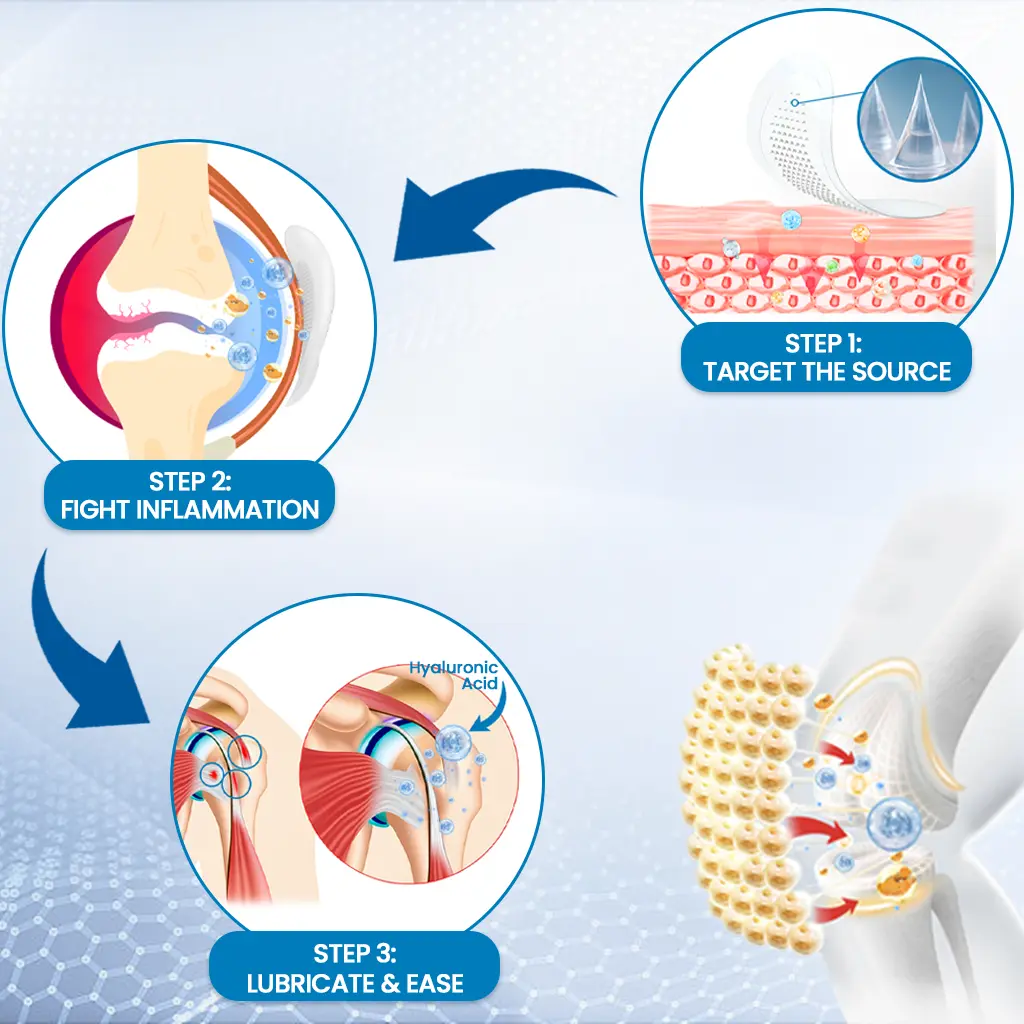

How It Works-Three-Step Joint Relief

Each Alisanda® Microdart is just 0.27mm long — 10 times thinner than a needle. It penetrates only the skin’s outer barrier (stratum corneum), without reaching pain receptors or blood vessels.

As the patch dissolves, the active ingredients penetrate the tissue — exactly where joint discomfort starts.

💧Hyaluronic Acid– Replenishes synovial fluid that cushions joints, literally “re-oiling” stiff movement

🌿Curcumin– Blocks inflammatory pathways causing swelling and morning stiffness